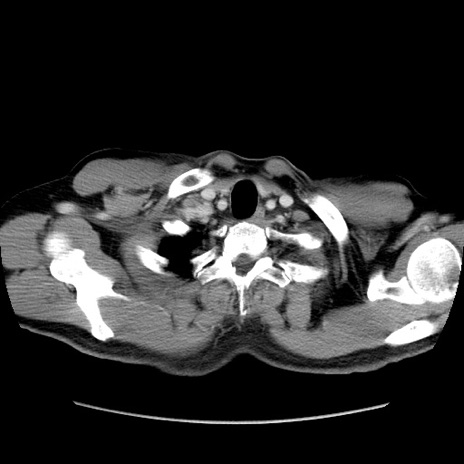

冠状断像

矢状断像

症例34(横断像)

【症例】60歳代 男性

【主訴】右鼠径部膨隆

【現病歴】1年程前より右鼠径部膨隆あり。自己にて還納可能だったため放置していた。3時間前より右鼠径部の脱出を認め、還納困難となり受診。

【既往歴】高血圧

【身体所見】右鼠径部に小児頭大の膨隆あり。弾性硬であり、用手還納は困難。左鼠径部にも膨隆を認める。脱出はなし。

【データ】WBC 15500、CRP 測定なし